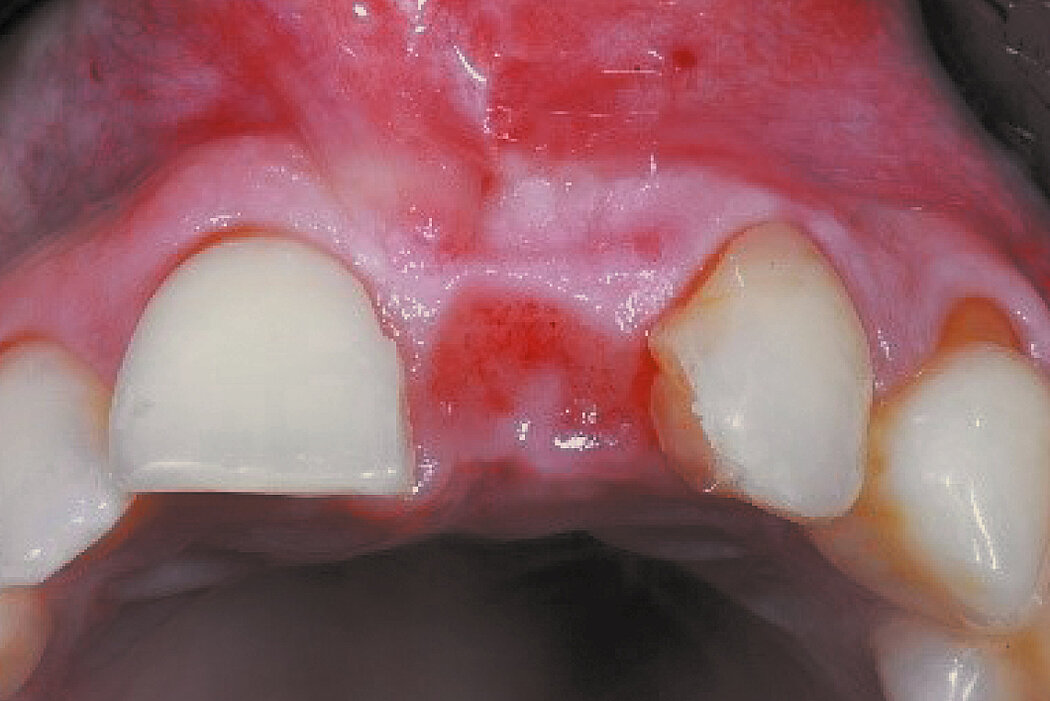

延迟种植的前牙区牙槽嵴保存

病例来自 Prof. Ronald E. Jung

瑞士,苏黎世

目的/方法

前牙区牙齿拔除后的硬组织和软组织保存,以便进行延迟种植。防止在植入种植体时进行广泛的引导骨再生手术。

结论

与自然愈合相比,使用Geistlich Bio-Oss® Collagen 和 Geistlich Mucograft® Seal 可以更好地保存硬组织和软组织。在植入种植体时,行微创GBR,对牙槽嵴进行塑形。

拔牙后即刻与拔牙后10个月的比较